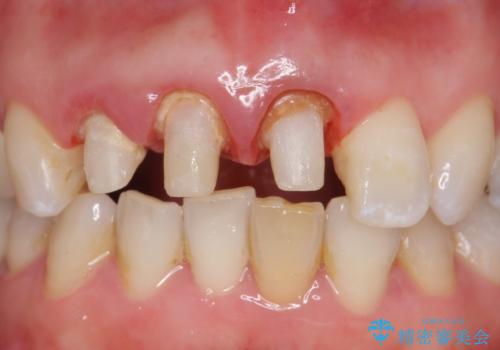

- 前歯の長さが違うのが気になるといらっしゃった方の症例です。

根尖病変を認めたため再根管治療を行った後、オールセラミッククラウン(スペシャル)にて補綴を行いました。

歯肉の腫れをより改善するため歯周外科を提案しましたが希望されませんでした。